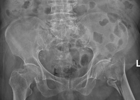

“原本以为老人年纪大了,这次骨折可能熬不过去,没想到在你们的全力救治下,老人恢复得这么好,真的太感谢你们了!”在我院骨科一区,莫婆婆的家属激动地向医护团队表达了深深的感激之情。 近日,我院骨科团队凭借精湛医术与多学科协作,成功为一位身患多种疾病的94岁超高龄患者实施股骨粗隆间骨折闭合复位内固定微...2025-06-13